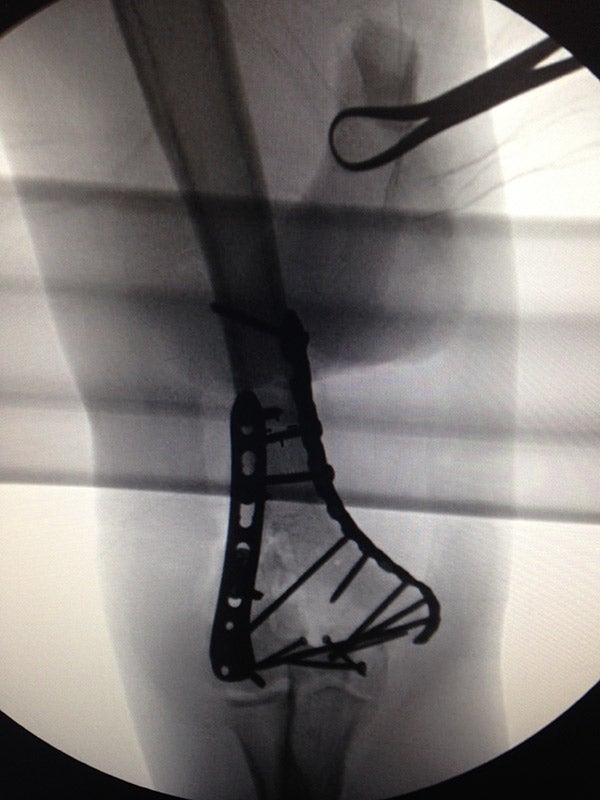

Bono experienced a bicycle accident in New York in 2014 -- and shared this photo of a titanium plate in his elbow.